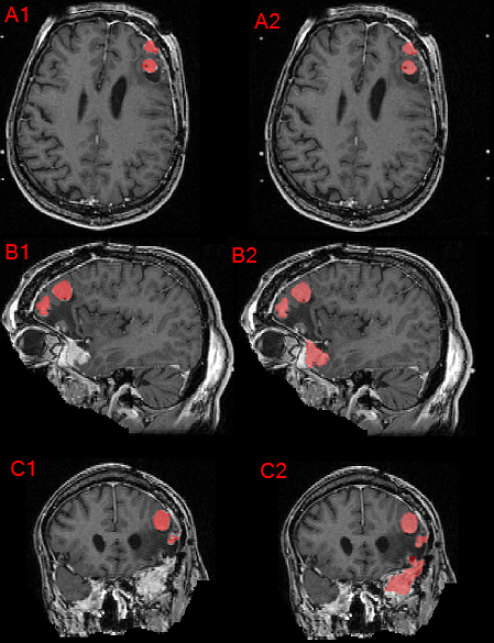

Refer to caption

Figure 9: Axial, sagittal, and coronal brain MRI of a patient with multiple meningioma demonstrating the difference between the provided institution’s GTV as seen in panels A1, B1, and C1 compared to the manually revised target label as seen in panels A2, B2, and C2. Note that corrections were made regarding inclusion of additional meningioma, correction of label edges, and inter-axial slice label smoothening.